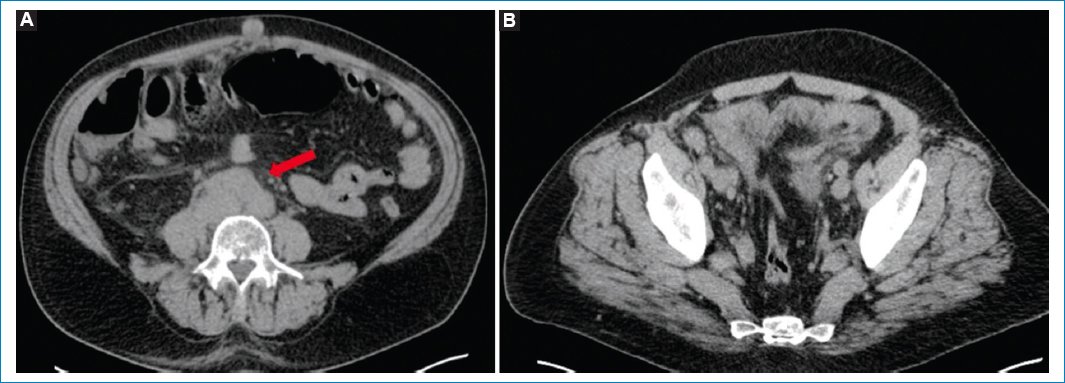

Existen algunos hallazgos asociados a los mencionados que deben inclinar la sospecha diagnóstica hacia la LP, como la presencia de adenomegalias múltiples y en diferentes niveles, nódulos peritoneales más grandes que en la carcinomatosis (en general masas), compromiso de la raíz del mesenterio y del intestino delgado, y esplenomegalia11,2931 (Figs. 2 y 3).

Figura 2. TC sin contraste endovenoso en un caso de LP, con hallazgos que respaldan la sospecha del diagnóstico. Nótense las adenomegalias retroperitoneales y pelvianas (flecha en A), los nódulos peritoneales múltiples y el grosero engrosamiento peritoneal (B).

Figura 3. TC sin contraste endovenoso en un caso de LP, con hallazgos que apoyan la sospecha del diagnóstico. Compromiso del intestino delgado evidente en la imagen coronal (flecha en A) y esplenomegalia asociada (B).